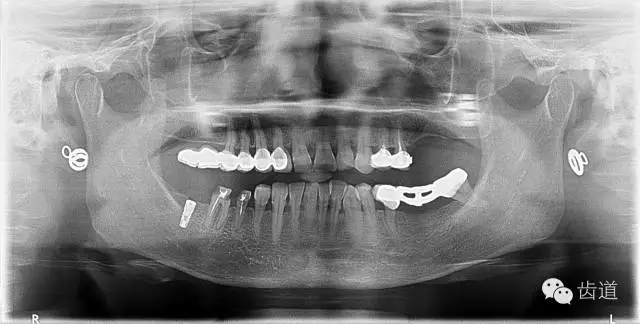

6、26,27,47種植修復(fù)(2014年1月)

4、 全景片

2、治療后